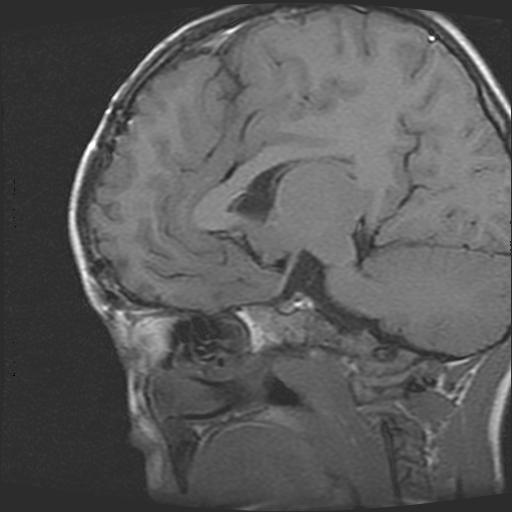

标题: PED0377: 6岁小儿,左侧视神经瘤术后 [打印本页]

标题: PED0377: 6岁小儿,左侧视神经瘤术后

6岁小儿,左侧视神经瘤术后。现左侧视力减退。